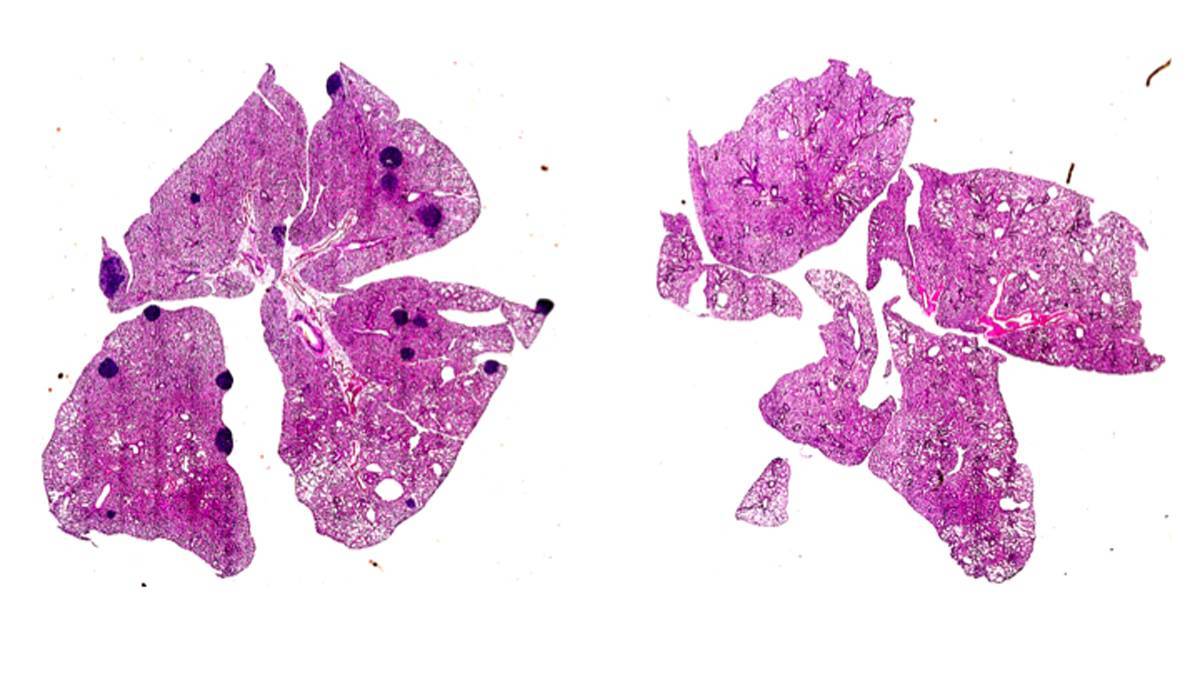

Los ratones con tumores mamarios desarrollaron metástasis en los pulmones (visibles como manchas oscuras), mientras que esto se previno en los ratones sin el gen ARHGEF1, una proteína clave implicada en la supresión de la inmunidad de las células T por el factor de coagulación tromboxano A2. / Jie Yang

«Los ratones con tumores mamarios desarrollaron metástasis en los pulmones (visibles como manchas oscuras), mientras que esto se previno en los ratones sin el gen ARHGEF1, una proteína clave implicada en la supresión de la inmunidad de las células T por el factor de coagulación tromboxano A2. / Jie Yang»;

Pero esas células T con el gen ARHGEF1 activado están dormidas, incapaces de reaccionar contra la invasión del organismo por el cáncer. Así, el objetivo de los investigadores era encontrar y neutralizar la señal responsable de esa activación del gen. Dicha señal resultó ser el TXA2, el mismo compuesto que las plaquetas producen para agregarse en la coagulación sanguínea, y cuya síntesis puede inhibirse por medio de la aspirina.